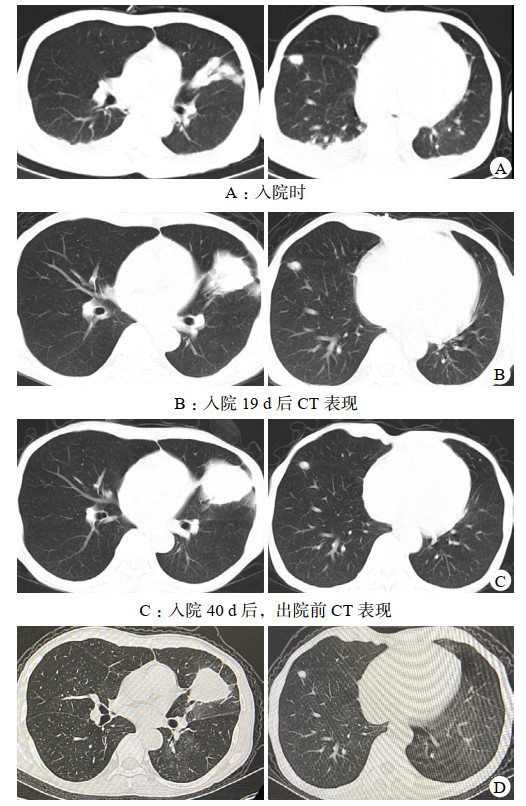

尿常规:蛋白4+,红细胞+,白细胞+;血常规:白细胞4.21×109/L,淋巴细胞百分比2.4%,中性粒细胞百分比90.7%,血红蛋白67 g/L,血小板69×109/L,CRP 30.3 mg/L;血生化:PCT 2.3μg/L,白介素-6 36.59 ng/L,白蛋白27.3 g/L,球蛋白21.4 g/L,尿素48.1 mmol/L,肌酐806.9 μmol/L,总二氧化碳17.5 mmol/L;免疫球蛋白G 8.38 g/L;CD3+T 141个/uL,CD4+T 69个/uL,CD8+T 64个/uL,CD20+B 9个/uL;CT:两肺可见大片状及结节样实性密度影,左肺上叶下舌段病灶内可见支气管充气征(图 2A);

| 图 2 患者入院与出院后CT影像 |

患者入院当日停吗替麦考酚酯、他克莫司,强的松减量至10 mg每日1次口服,隔日血液透析,送检血液mNGS,次日报告:马尔尼菲蓝状菌(序列数4 794)、人类疱疹病毒5型(序列数42)(入院10日后血培养、中段尿培养报马尔尼菲蓝状菌,痰培养、痰浓缩集菌抗酸菌检测阴性)。查血液真菌G试验28.82 pg/mL,GM试验2.59,血液INF-γ释放试验阴性。予莫西沙星0.4 g每日1次静滴、伏立康唑0.2 g每日2次静滴、两性霉素B脂质体(峰克松)逐步加量至50 mg每日1次静滴联合抗感染,监测伏立康唑血药谷浓度3.53 μg/mL,17 d后停两性霉素B脂质体。期间双眼结膜红肿充血加重,伴不自主流泪,右鼻翼、鼻腔、左侧嘴角处溃疡扩大,先后加用妥布霉素滴眼液、卡波姆滴眼液、金霉素眼膏、莫匹罗星软膏外涂。入院19 d后仍有间断发热,CRP升至44.6 mg/L,PCT升至4.32 μg/L,复查CT左肺上叶见类圆形及斑片状密度增高影较前增大,右肺下叶叶间裂处可见多发斑片状密度增高影(图 2B)。行支气管镜检查,术中左舌叶上侧支一亚支可见球型新生物堵塞管腔,表面粗糙,触之易出血(图 3),病理活检示组织急慢性炎症,局部见大量泡沫样组织细胞反应,抗酸染色未发现阳性菌(图 4)。肺泡灌洗液(BALF)GM试验0.84,BALF mNGS报烟曲霉(序列数11),马尔尼菲蓝状菌(序列数5),哥伦比亚分枝杆菌(序列数4989),人类疱疹病毒5型(序列数162),人类疱疹病毒4型(序列数6)。痰液及BALF分枝杆菌培养均阴性。明确诊断为“⑴播散性马尔尼菲蓝状菌病;⑵肺非结核分枝杆菌病(哥伦比亚分枝杆菌);⑶侵袭性肺曲霉菌病(烟曲霉)”。考虑利福平显著影响伏立康唑血药浓度,未加用利福平。抗感染方案调整为伏立康唑0.2 g每日2次静滴、乙胺丁醇0.75 g每日1次口服、阿奇霉素0.5 g每日1次口服、利奈唑胺0.6 g每日2次静滴。患者静滴利奈唑胺期间出现胸闷、恶心,停利奈唑胺,恢复莫西沙星0.4 g每日1次静滴,监测体温峰值逐步下降,出院1周前未再发热。在院43 d,出院前CRP 1.1 mg/L,PCT 0.342 μg/L,血液真菌G试验9.9 pg/mL,GM试验0.22,CD4+T 143个/uL,双侧眼睑红肿好转,右侧鼻翼、鼻腔及左侧嘴角溃疡消退(图 1b)。复查CT左肺上叶、右肺下叶叶间裂处仍见高密度影(图 2C)。患者出院后继续口服伏立康唑、阿奇霉素、乙胺丁醇、莫西沙星抗感染,期间未再发热,常规血液透析治疗,3个月后复查CD4+T 314个/uL,CT左肺上叶团块影和右肺下叶叶间裂结节体积较前明显缩小(图 2D)。